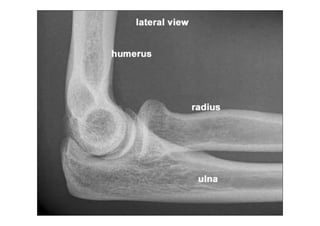

RADIOLOGIA DO

TRAUMA DO ESQUELETO

Referência: http://www.accessexcellence.org/RC/VL/